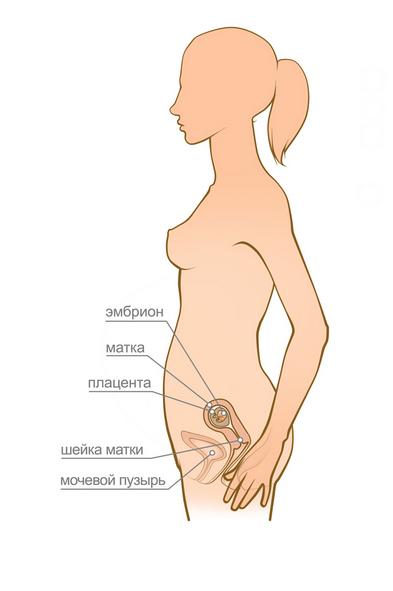

У разі позаматкової вагітності терміново потрібне оперативне втручання. У таких випадках високий ризик, що зростаючий плід може викликати розрив маткової труби, що призведе до сильної кровотечі, що загрожує летальним результатом. Якщо у вас коричневі виділення, біль внизу живота, можливо спочатку одностороння, потім розповсюджується на весь низ живота, якщо біль посилюється при кашлі, супроводжується нудотою і блювотою, це може вказувати на позаматкову вагітність. В цьому випадку зволікати не можна, необхідно викликати швидку допомогу і відправлятися в лікарню.

вагітність - Це складний фізіологічний процес, який може супроводжуватися різними ускладненнями, в тому числі і такими, які викликають маткові або вагінальні кровотечі. Як правило, найбільш небезпечні з цієї точки зору перший і останній триместр вагітності, точніше, найперші і останні її тижні.